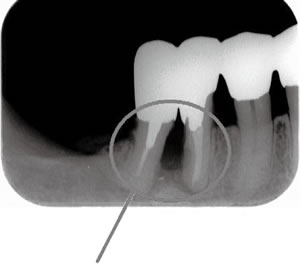

■X線検査

X線で撮影することにより、目では見えない歯肉の下の顎の骨の状態を確認します(写真2)。また、歯石の沈着状況や顎の骨の溶け具合などを診断します。